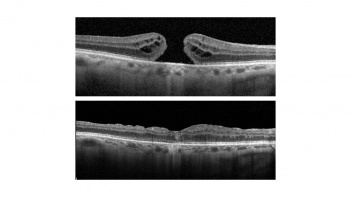

Inverted flap technique (or inverted internal limiting membrane flap technique) for macular hole closure.

In 1991, Kelly and Wendel [2] described the first surgical approach to this condition which, until then, was considerable untreatable. The rational of the surgery was the identification and treatment of vitreoretinal traction forces, either tangential, anteroposterior or both. Ever since, the treatment strategy has been improving and currently most of macular holes (around 85-90%[1]) can be successfully closed using a procedure involving pars plana vitrectomy, dye-assisted internal limiting membrane peeling, and gas tamponade. However, for some macular holes such as those which are large, chronic, or associated with myopia, surgical failure is more commonly seen. In fact, the rate of persistent macular hole varies between 8-44%[1] in literature. In 2010, Michalewska et al[3] introduced the inverted flap technique, thus providing a new surgical approach to overcome these challenging scenarios. On their original description of the inverted flap technique, Michalewska et al reported a 98% closure rate of large macular holes (defined as > 400 µm, according to the classification in the International Vitreomacular Traction Study[4]). As the success of the procedure was broadly demonstrated since the beginning, the indications and applications of the technique have grown, surpassing the previous standard procedures in selected situations.